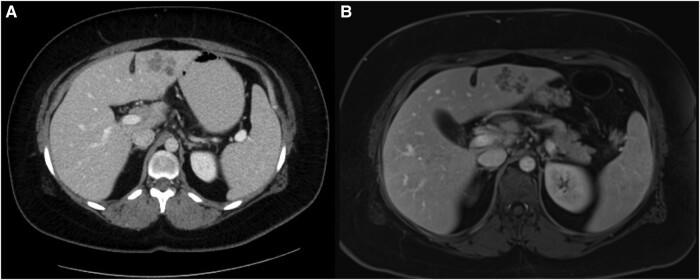

is a trematode causing acute and chronic infection. A 33-year-old Canadian woman with eosinophilic liver abscesses and no relevant travel was diagnosed with infection is reported in livestock in Alberta. This is the first case of locally acquired fascioliasis in Canada in >100 years.

https://cdn.ncbi.nlm.nih.gov/pmc/blobs/c8ef/10933217/045d8bc8d575/ofae101f1.jpg